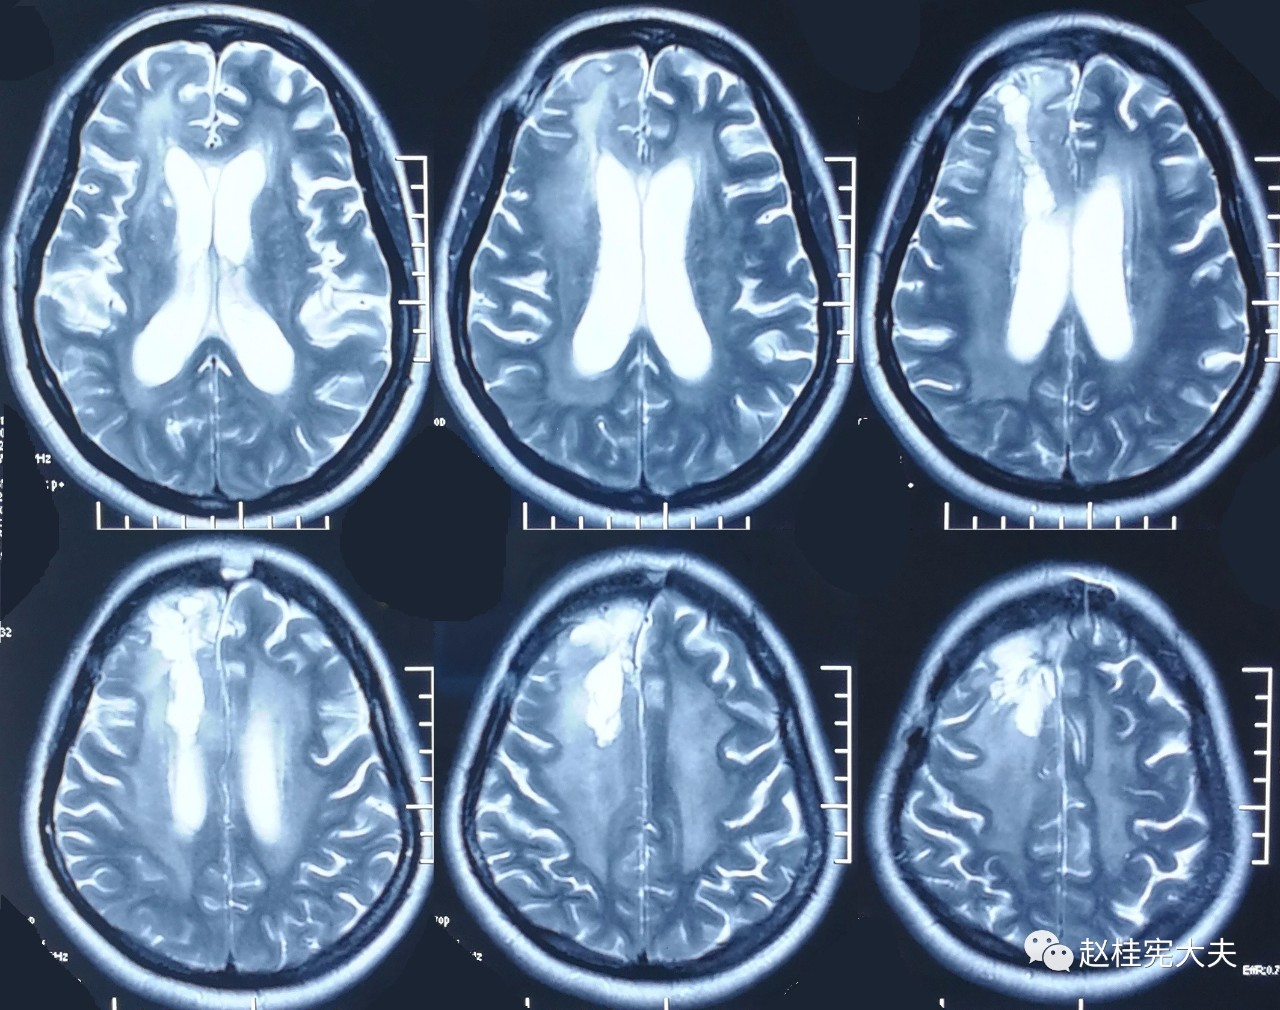

为了更直观,我们先看看其中1例患者的脑白质病变影像学的改变吧:

2017.10

可以看到,随着时间的延长,脑白质的T2异常信号范围不断扩大,并且出现了脑室扩大,脑萎缩。